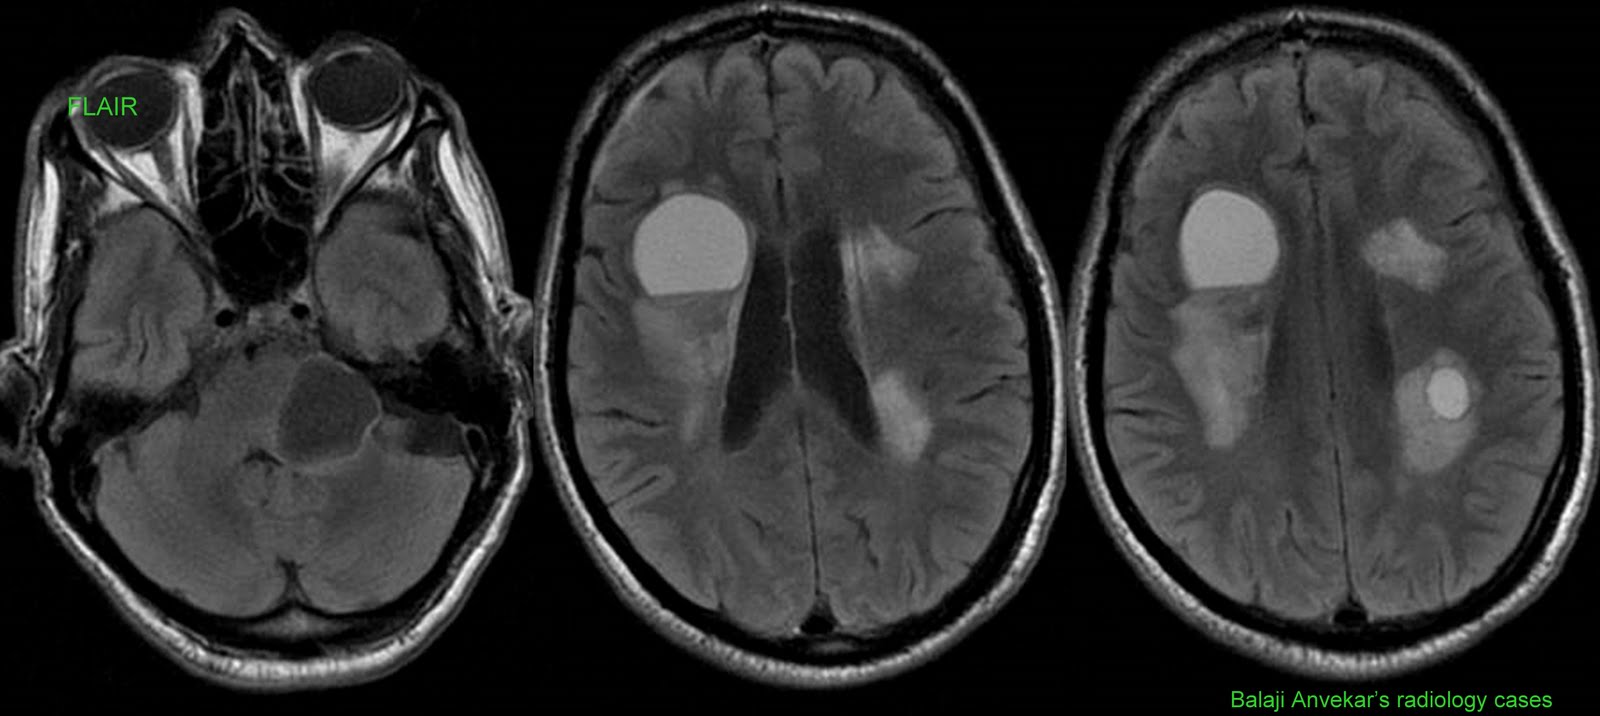

From radiocases.blogspot.com

Dr Balaji Anvekar's Neuroradiology Cases Hydatid cysts brain Velum Interpositum Cyst Brain A common, usually asymptomatic, and incidental finding for cvi. a less frequently seen variant is the cavum of the velum interpositum. midline cysts occur in the interhemispheric region of the brain and have a circular or elliptical shape. Hearing loss and was referred to rule out acoustic neuroma. in the brain, the cavum veli interpositi (cvi) is. Velum Interpositum Cyst Brain.